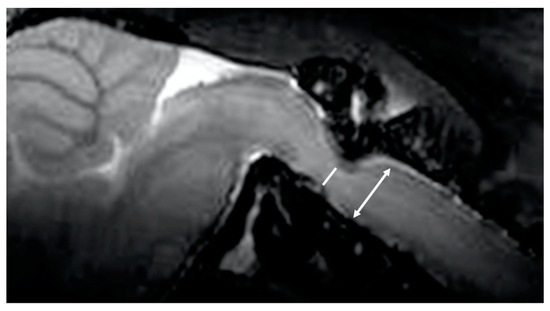

2.5. Histological Analysis

3.6. Histological Assessment

The histopathological examination of the spinal canal in craniovertebral lesions of 17-week-old twy/twy mice showed significant ossification and resulting compression of the spinal cord, which strongly suggested the presence of decreased CSF flow (Figure 6).

Figure 6. Histological evidence of significant ossification and compression of the spinal cord in twy/twy mice (*). (A) Microphotographs of hematoxylin and eosin (H&E)-stained sagittal sections of the cervical spine of 17-week-old twy/twy mice. (B) T1WI sagittal MRI showed obvious spinal cord compression resulting from ectopic calcification. (C) T2WI sagittal MRI showed obvious spinal cord compression resulting from ectopic calcification.